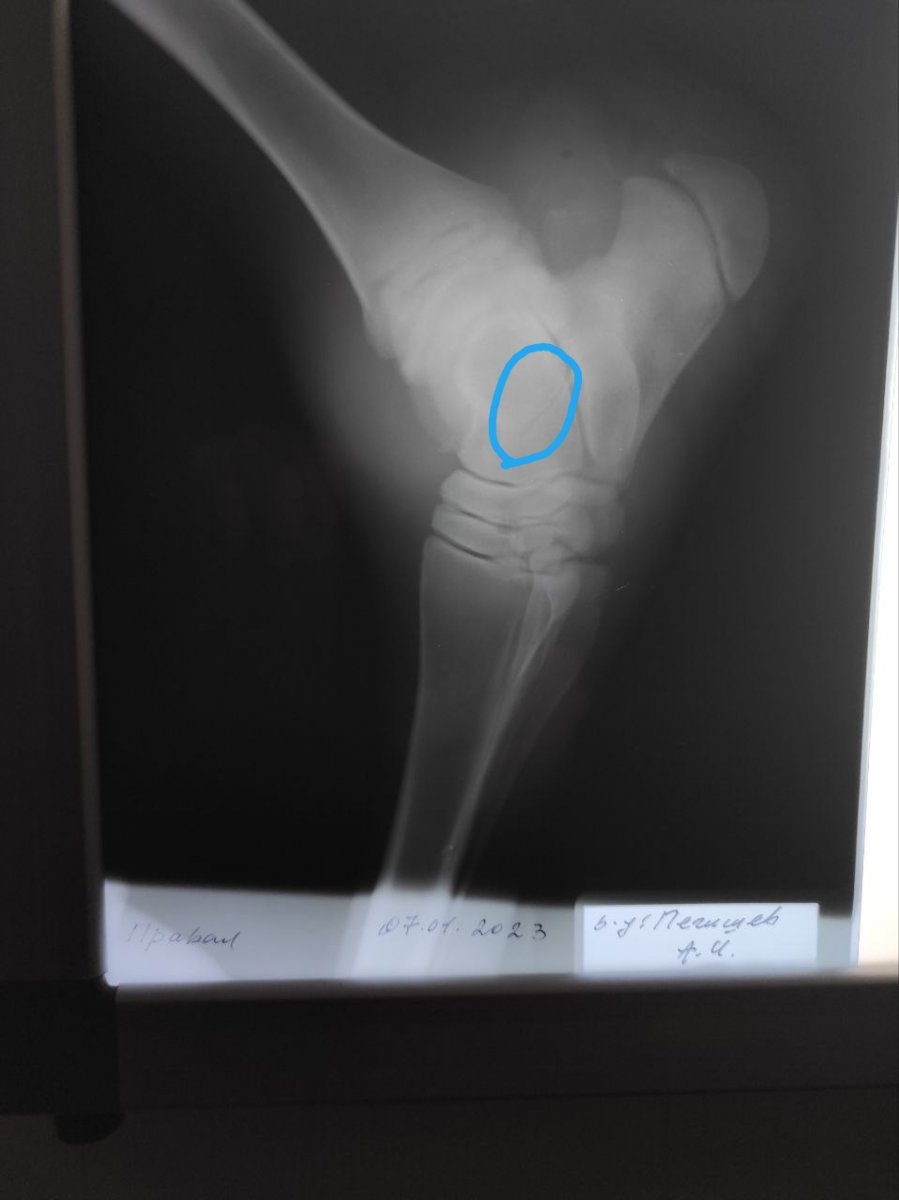

1,2 фото - нога на момент первого осмотра, 3,4 фото - на 8-ой день лечения, 5 - тот самый свищ, 6,7,8,9 - рентген перед лечением